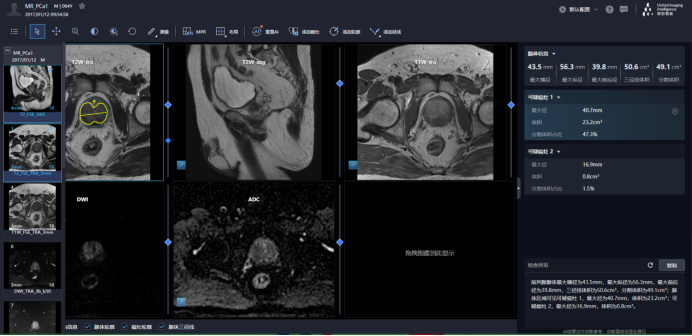

联影智能前列腺人工智能诊断系统支持多序列联合阅片,帮助医生从更多维度更精准更高效的判读前列腺癌病情;还可以智能分割腺体和可疑癌灶,并对腺体、病灶进行智能定量分析,然后根据分析结果自动生成检查所见,并一键复制到RIS系统。

同时,联影智能前列腺人工智能诊断系统也支持多种智能编辑工具,便于医生标注重点内容;还能智能生成结构化图文报告,个性化设计更复合医生日常报告逻辑,大幅度节省书写报告时间,一目了然的图文形式也减少了医患沟通的成本。全方位提升诊疗效率。